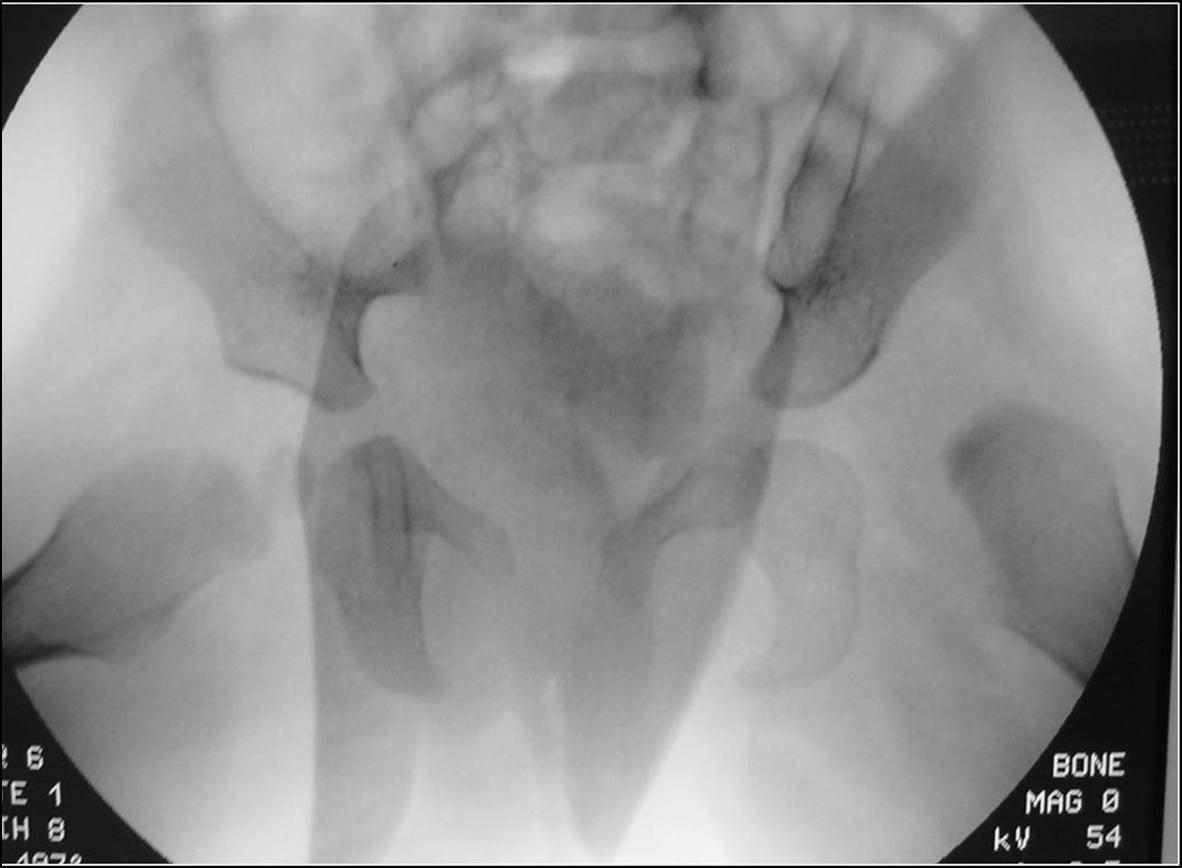

In rari casi, anche con il confezionamento di un gesso, la riduzione non è ottenuta, ad indicare la presenza di ingombri fisici che ne impediscono la riduzione. L’unico modo per ripristinare la congruenza articolare è rimuoverli con un intervento chirurgico mirato. A seguito l’immobilizzazione in gesso permette la formazione di una cicatrice resistente, mantenendo in sede i capi articolari.

In questi casi si ricorre a soluzioni chirurgiche che associano tempi sui tessuti molli e sulle strutture ossee. Vengono per cui presi in considerazione osteotomie femorali o di bacino, acetabuloplastiche per migliorare la continenza acetabolare, tenotomie degli adduttori e ritensionamento capsulare.